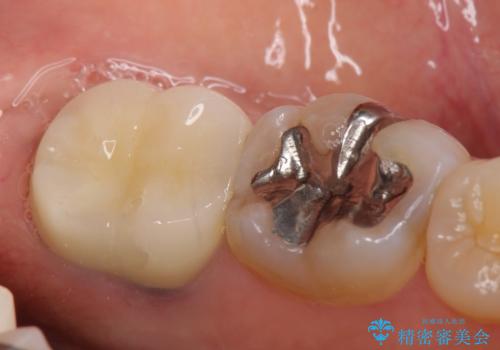

今回用いたオールセラミッククラウンはジルコニアフレームという白い素材の上にセラミックを盛っているため、審美性が非常に高いのが特徴です。

また、ジルコニアは人工ダイヤモンドの材料にも使われているほど高い強度を持っており、そのためオールセラミッククラウンは審美性だけでなく、奥歯やブリッジの補綴も可能とするクラウンです。